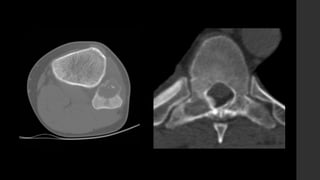

Tumor de Células Gigantes.

Murphey MD, Nomikos GC, Flemming DJ et-al. From the archives of AFIP. Imaging of giant cell tumor and giant cell reparative granuloma of bone: radiologic-pathologic correlation. Radiographics. 21 (5): 1283-309.

• Se localizan en huesos largos y sólo en núcleos de osificación cerrados, cercanos a

la superficie articular (84 – 99% <1cm).

• Son lesiones bien definidas excéntricas con margen no esclerótico.

• RX y TC 

 Zona de transición delgada sin esclerosis periférica.

 La corteza adyacente está adelgazada, expandida o deficiente.

 Reacción perióstica sólo en 10 - 30% de los casos.

 Puede presentar masa de tejidos blandos.

 Puede haber fracturas patológicas.

 No presentan matriz calcificada.